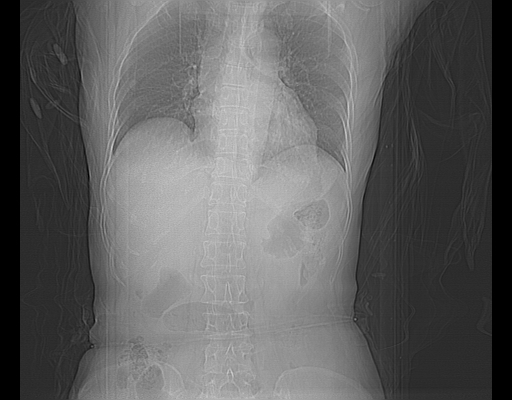

标题: CT16642:男62岁,突发性上腹部疼痛来诊。请讨论!

2008-6-10ct平扫

6月片:肝血管瘤并破裂出血?肝左外叶囊肿

考虑为肝血管瘤破裂出血并肝包膜下血肿;右侧少量胸腔积液。

6月份ct片显示肝内巨大混杂密度团块,伴包膜下积液(内含液液平面),增强多无明显强化。只能考虑肝占位病变,并肝内、血膜下血肿。肝ca并出血多见,而肝血管瘤并破裂出血少见。